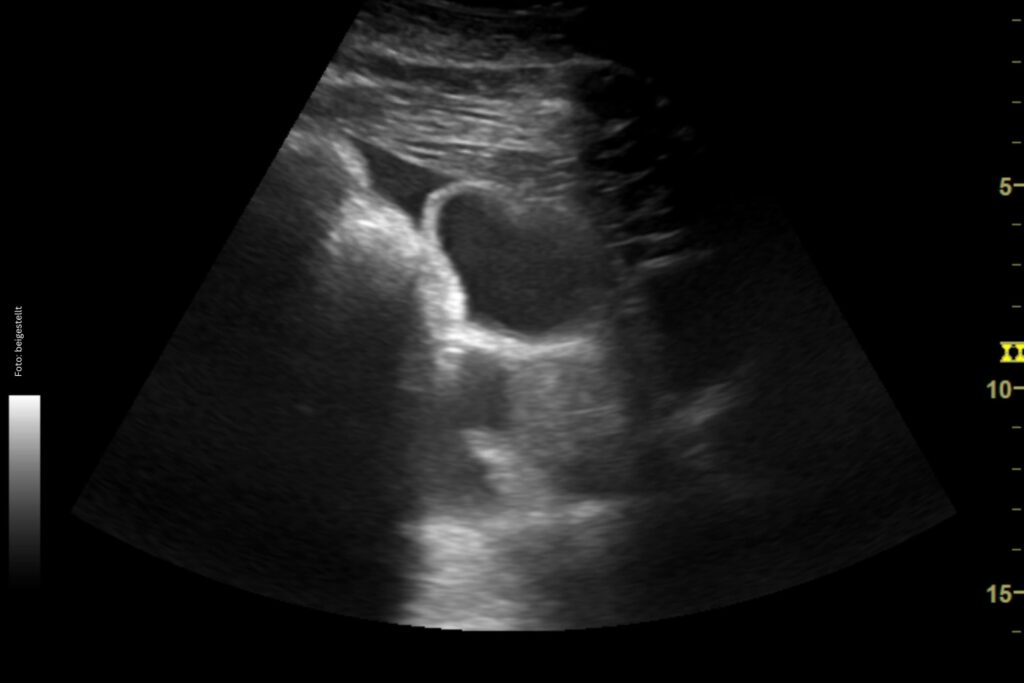

Der nächste Schritt ist ein Abdomenultraschall: Hier ist bei einer IBD eine Verdickung der Darmschleimhaut zu erwarten. Die Dünndarmschleimhaut sollte ja drei bis vier Millimeter dick sein. Ein Wert über 5,7 mm zeigt deutlich an, dass etwas nicht in Ordnung ist. Außerdem achte ich darauf, ob die Veränderungen gleichmäßig verteilt sind oder nur einzelne Darmschlingen stark verdickt sind. Ein weiterer diagnostischer Schritt ist die Abdominozentese: Hier werden das Totalprotein, die Gesamtzellzahl sowie das Laktat gemessen. Dies ist auch wichtig, um ein Lymphom, eine weitere Differentialdiagnose, ausschließen zu können, wobei hier das Bauchhöhlenpunktat auch unverändert sein kann. Bei den meisten Pferden mit IBD ist das Totalprotein nicht verändert.